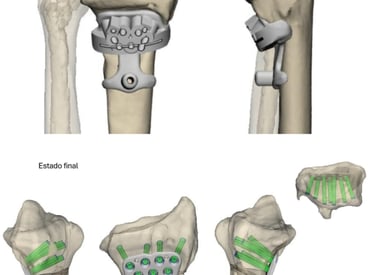

Planificación con impresión 3D

Impacto de los avances en pacientes y profesionales médicos.